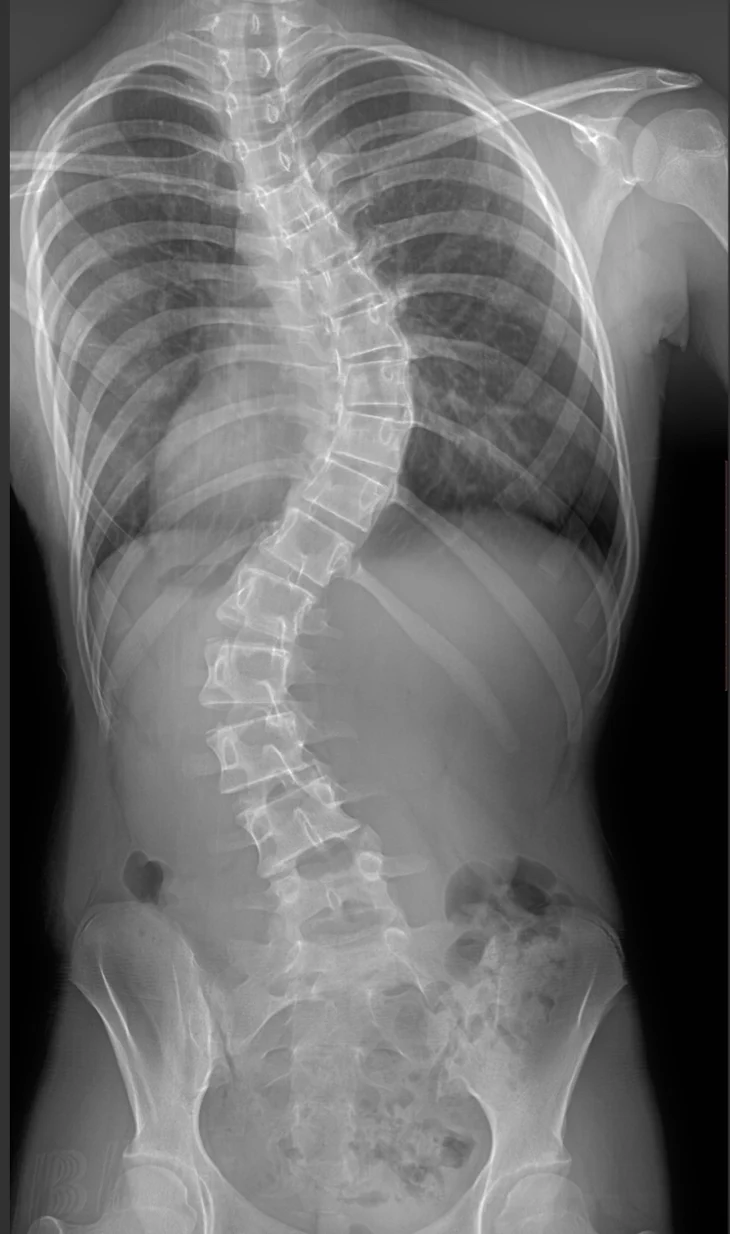

First Certified Postural Restoration Center and Schroth-based Certified Scoliosis Physical Therapy Rehabilitation Center in North Carolina

Many practices advertise Postural Restoration or Schroth-based approaches, however, Advance Physical Therapy currently employs SIX Fully Credentialed Postural Restoration Clinicians. Advance Physical Therapy also employs the first practitioners certified in the Schroth-based Barcelona Scoliosis Physical Therapy School Method (BSPTS) in the entire state of North Carolina. Please inquire carefully about the qualifications of practitioners advertising Postural Restoration or the “Schroth Method”. Certified Postural Restoration Therapists are designated with a PRC or PRT. Schroth-based practitioners will have a certification which demonstrates intensive education in the approach.